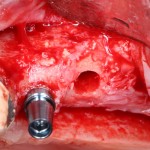

Синуслифтинг: что делать при перфорации слизистой оболочки гайморовой пазухи?